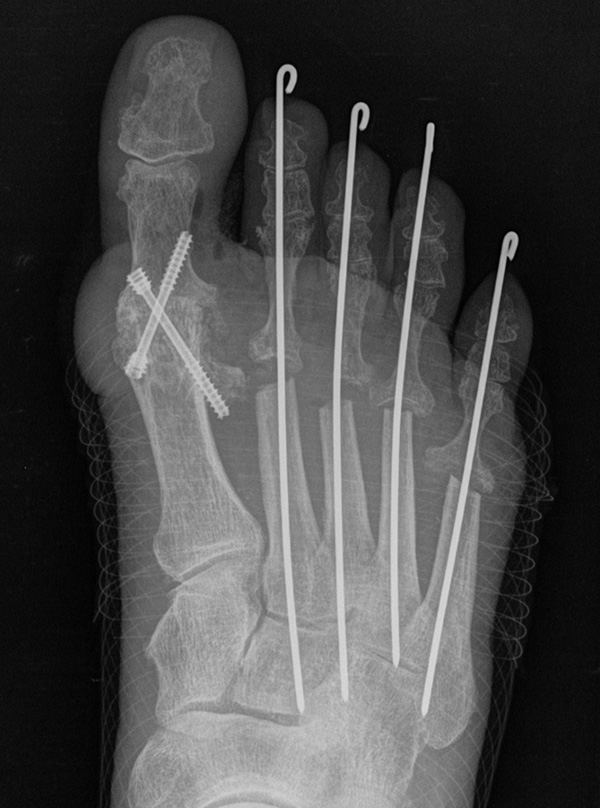

Zum Lesen der Bildbeschreibung und zur Vollansicht bitte das Bild anklicken.

Deutlich bessere Ergebnisse wurden erreicht durch eine Kombination der OP nach Tillmann mit einer Arthrodese des Großzehengrundgelenks oder auch einer Lapidus-Arthrodese 611. Dies wurde bereits 1956 durch Vainio empfohlen, hat sich aber erst in diesem Jahrtausend flächendeckend durchgesetzt 121314.

Die Operation nach Hoffmann-Tillmann (Abb. 4) ermöglicht durch die Resektion der Metatarsaleköpfe die Reposition der Zehen, da hierdurch der notwendige Platz geschaffen wird (Tillmann 1990). Meist sind nicht nur die knöchernen Strukturen der Metatarsaleköpfe destruiert, auch das plantare Polster ist disloziert, regelmäßig kommt es zur Ruptur der plantaren Platten mit Destruktion der Kapsel-, Band- und Sehnenstrukturen (Tillmann 2009) 6. Häufig findet man ausgeprägte Rheumaknoten oder Bursitiden plantar. Durch die breite, querovaläre Hautexzisionaus dem Vorfußballen werden plantare Schwielen entfernt, später beim Hautverschluß werden die plantaren Strukturen durch die plastische Dermatodese wieder in die Belastungszone reponiert.

Es sollten immer alle MT Köpfe II-V reseziert werden, um einen harmonischen Metatarsale Index mit genauer Längenabstimmung herzustellen und keine Druckspitzen durch überlange Metatarsalia zu provozieren. Die kann in Einzelfällen bedeuten, dass ein weniger destruiertes Gelenk zwischen oder am Rand der metatarsalen Reihe geopfert werden muss. Die Operation nach Hoffmann-Tillmann wird meist ab LDE Stadium IV und V indiziert (Tabelle 1).